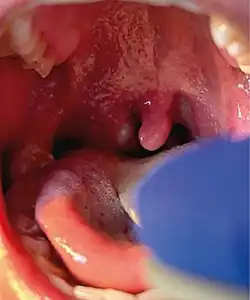

Right tonsillar enlargement with an overlying pustular lesion during the outbreak

Unusually, none of these new cases had any known contact history with the previous three confirmed cases, which suggested a kind of transmission that had not been seen before,[71] a wider community transmission of the virus in the London area. The UKHSA stated that the risk to the general public remained "very low".[70][72] Patients with active mpox infection were confirmed to be hospitalised at the Royal Victoria Infirmary in Newcastle upon Tyne and at the Royal Free Hospital and Guy's Hospital in London.[70]